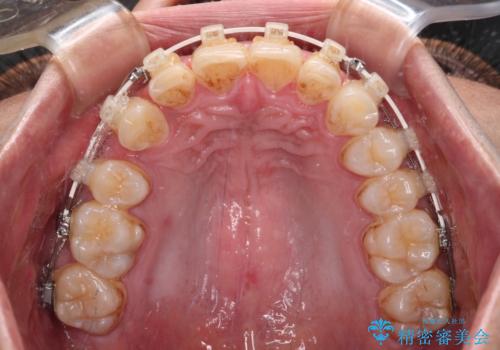

- 審美装置

- 深い咬み合わせと前歯のデコボコを改善したいとのことで来院された患者様です。

口元の突出感はないものの、上顎前歯のデコボコが著しく、右側の咬み合わせがずれていたため、上顎右側第一小臼歯1本を抜歯することとしました。

咬合力が非常に強く、抜歯したスペースがなかなか閉じないであろうことは予想できましたが、思っていた以上に期間がかかりました。